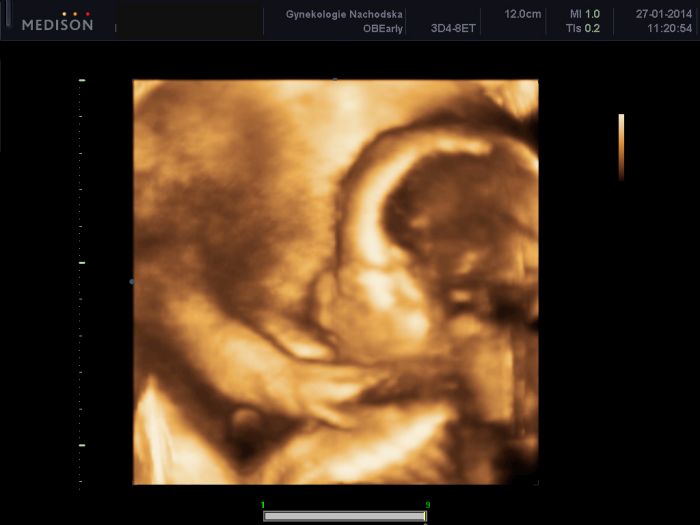

Ahoj holky moje :-) Tak prohlídka u mé Dr. proběhla v pohodě, žádný problém nevidí, a zatím stále ještě ani nevidí pindíčka, takže stále to vypadá na Emu. Ale uvidíme, jak zítra na velkém UZ. Váhový odhad je už přes 530g...takže bude asi bude větší jak Anička, toho se děsím. Jinak vše ok. A samozřejmě přikládám to naše dítko v celé své kráse :-)